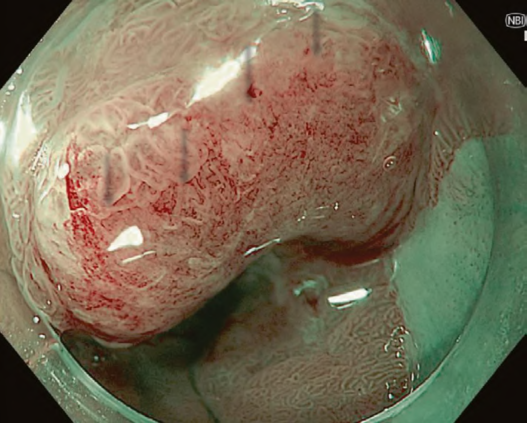

Between the late 1980s and early 1990s, research on image processing and analysis was conducted mainly by the National Cancer Center Hospital East and Olympus Group, which led to basic experiments on narrow band light imaging starting in 1994. As a result, a patent application was made in 1999, and a narrow band imaging (NBI) device (Olympus Co., Tokyo, Japan) was introduced commercially in 2006. Since the early 2000s, it has been demonstrated by a number of researchers that NBI is useful for early diagnosis of cancers of the oropharynx, hypopharynx, esophagus, stomach, and large intestine. A succession of similar techniques was later made public, and interpretation of the term “special light observation” began to differ among academic societies and research organizations. In view of this problem and the need to establish internationally applicable terminology for endoscopy, we proposed an object-oriented classification for endoscopic imaging in 2008. Basically, the concept was that endoscopic imaging can be divided into five categories: (1) conventional endoscopy (white light endoscopy (WLE)), (2) image-enhanced endoscopy (IEE), (3) magnified endoscopy, (4) microscopic endoscopy, and (5) tomographic endoscopy [1].

While NBI has spread and contributed to the standardization of diagnosis on a global level, our colleagues have worked tirelessly to further improve the quality of endoscopy. Over the last 15 years, owing to the development and worldwide spread of NBI, international classifications have been introduced in the field of gastric cancer, Barrett’s esophagus, and colorectal neoplasia.

The LASEREO system (FUJIFILM Co., Tokyo, Japan) based on laser endoscopy was developed for advanced IEE, including WLI, BLI, and LCI. LCI using short-wavelength narrow band laser light combined with white laser light is a new technique that enhances differences in red coloration through digital processing [2]. This enables LCI to visualize red lesions better by enhancing their intensity relative to whitish lesions, which appear whiter. Recently, a controlled, multicenter trial with randomization using minimization has reported that LCI is more effective than WLI for detecting neoplastic lesions in the pharynx, esophagus, and stomach [3].